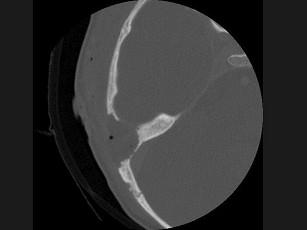

女性,17岁,右耳乳突区隐痛,右耳后乳突区出现包块,逐渐增大,CT检查如图所示,请选择最可能的 ( )